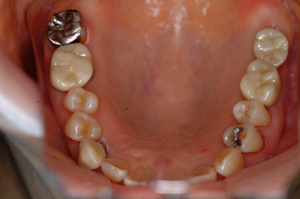

⑮ガイデットサージェリー(前顎に及ぶ歯槽骨非薄)